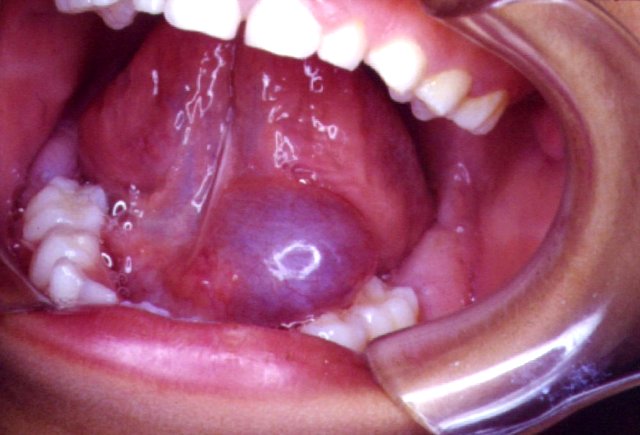

*Higroma quístico.